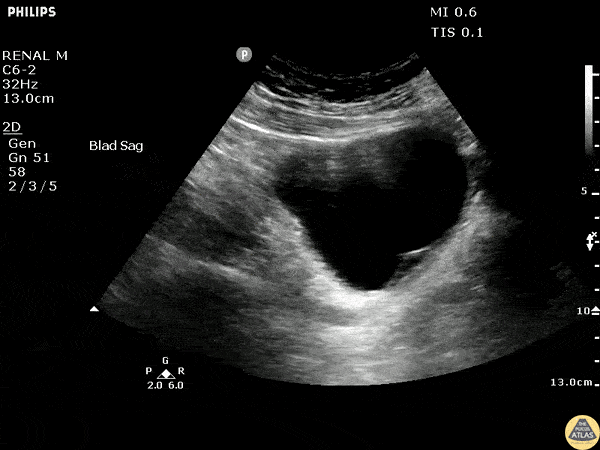

Renal/GU - Bladder Hematoma

Sagittal view of the bladder shows a post-procedural hematoma within the bladder wall obstructing one of the ureteric openings. Image courtesy of Robert Jones DO, FACEP @RJonesSonoEM Director, Emergency Ultrasound; MetroHealth Medical Center; Professor, Case Western Reserve Medical School, Cleveland, OH View his original post here